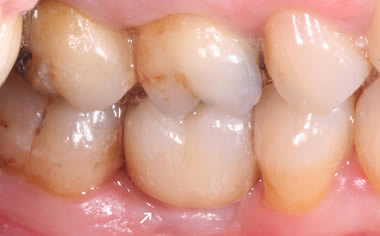

More back teeth replaced by dental implants

Case Three (2 images)

Case Four (4 images)

Case Five (4 images)